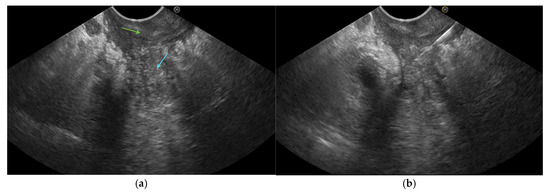

3.5. Pancreatic EUS

3.6. Management